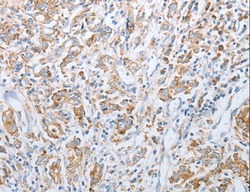

- Submitted by

- LSBio (provider)

- Main image

- Experimental details

- Immunohistochemistry of Human gastric cancer using KISS1R Polyclonal Antibody at dilution of 1:15.